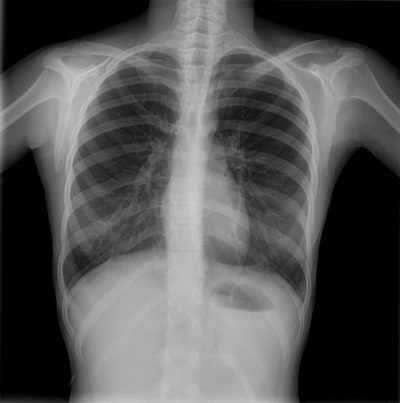

The vital signs and physical examination were normal, with the exception of a crepitations synchronous with the heartbeat upon auscultation (Hamman sign). The patient was evaluated with an electrocardiogram (ECG), chest radiograph, blood tests and a transthoracic echocardiogram. The ECG revealed a sinus rhythm of 68 bpm, a normal axis, the corrected QT interval of 0.38 and an early repolarization pattern. The chest radiograph revealed space between the parietal pleura and the pericardium at the left heart border (Figure 2). The complete blood count, chemistry panel, cardiac enzymes and coagulation tests were normal, echocardiogram with normal biventricular function, without chamber hypertrophy and no signs of cardiac tamponade.

| Figure 2. Case 1. Male adolescent aged 16 years who presented to the emergency department with precordial pain with onset 4 hours prior. Chest radiograph with separation of the parietal pleura from the pericardium in the left border of the heart (left image) and normal follow-up radiograph (right image) |

![]() |

The patient was hospitalized for 3 days and only required analgesia, with full resolution of symptoms and normal features in follow-up evaluations.